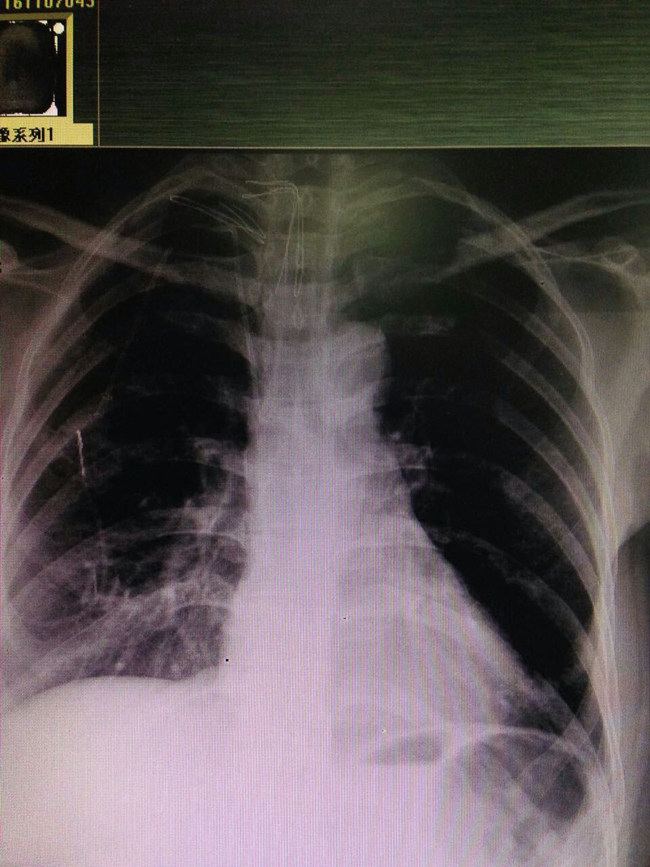

11月7日上午,在宋张骏院长的指导和手术二部,B超中心的全力配合下,乳腺病院二病区医生团队率先完成了乳腺病院首例静脉输液港植入手术。这名患者系乳腺癌术后复发,随即转入我科治疗,但由于胳膊水肿无法进行静脉输液及PICC置管术。为了能顺利的进行下一步治疗,宋张骏院长带领我科医生团队进行仔细评估后认为应进行手术放置静脉输液港。整个手术过程顺利,术后拍片查看输液港放置位置准确,患者无任何不适,成功解决了输液困难的问题。